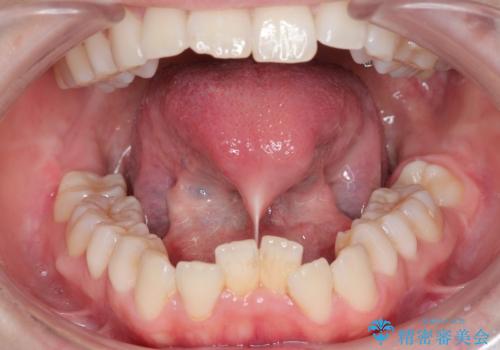

最新の症例

Latest cases